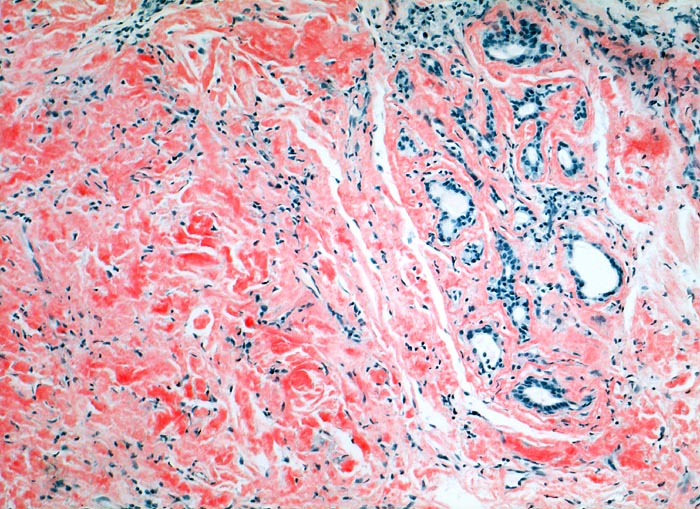

Lokalisierte Amyloidose

Larynx

Massenhaft kongorote Amyloidablagerungen im Stroma.

Immunhistochemisch AL-Amyloid

Bei der laryngealen Amyloidose handelt es sich oftmals um eine lokalisierte Erkrankung ohne Systembeteiligung. Sie kann zu heiserer Stimme oder Dyspnoe führen. Meist handelt es sich wie im vorliegenden Fall um AL-Amyloid. Nach einer Systembeteiligung sollte klinisch gesucht werden.